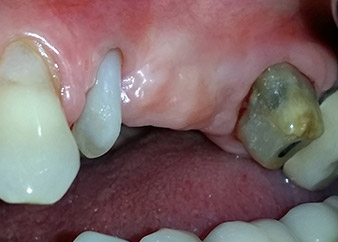

A 58-year-old female patient complained of pain and increased mobility of her bridge abutment tooth 24. Periodontal inflammation was present with pocket depths of 7 mm mesiobuccally and more than 12 mm distally, as well as third-degree furcation involvement. Moreover, the radiograph revealed an extensive periodontal lesion around the apical region of the (alio loco) endodontically pretreated tooth 24 (Fig. 1).

One year earlier, teeth 25 and 26 had been extracted due to trauma and for endo-perio reasons, prior to the placement of the bridge. A combined endo-perio lesion was diagnosed for tooth 24, of unclear aetiology. The patient wanted to keep her bridge abutment teeth 24 and 27 and would not accept a final, or even temporary, removable prosthesis. Therefore, it was agreed to make all efforts to retain both teeth, in spite of their poor prognosis as based on radiological and clinical findings.